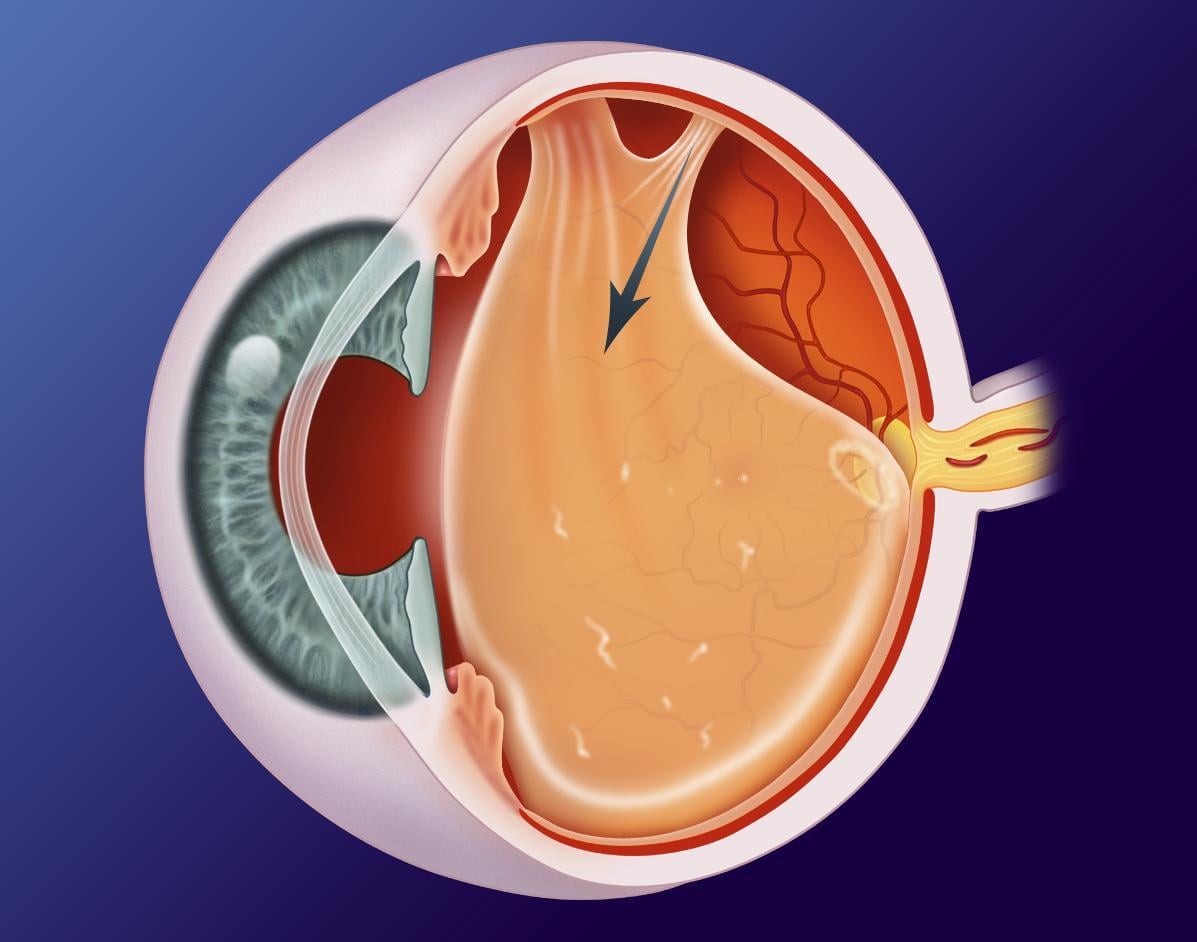

玻璃體是眼球內一個啫喱狀的組織,玻璃體會隨年齡增長而退化,慢慢液化、收縮,最後與視網膜完全分離,這就是玻璃體後脫離。收縮過程中有機會拉扯到視網膜,導致視網膜破洞甚至脫落,延誤治療可對視力造成永久性損害,嚴重可致盲。

我們視物就像目光透過一個金魚缸,如果水變得混濁,就會看到有半透明東西在眼前飄浮,這就是飛蚊症了。當玻璃體老化時會變得混濁,便會出現飛蚊症狀,若因玻璃體老化萎縮而撕扯到視網膜,視線就會出現閃光,像有人在用閃光燈拍照一般。如果視網膜因此而破洞,飛蚊症狀會急劇增加,也會出現閃光視覺,一旦有這些狀況發生,就要盡快求醫做眼科檢查,若然置之不理視網膜可能會完全脫落,導致視力驟降,或周邊視野有黑影,彷似戲院落幕一樣,嚴重甚至眼前有大片黑影,造成不可逆轉的視力缺失或失明。

如果只是玻璃體老化,與視網膜分離是毋須手術治療的,只需持續觀察視網膜有沒有破損情況,即使有飛蚊症狀亦屬正常。若不幸發現視網膜破洞,就要進行激光治療修補。病情惡化至視網膜剝落的話,治療手術會更複雜,若液體流到黃斑點,部分視力損傷即使手術也不能逆轉,所以盡早求醫非常重要。